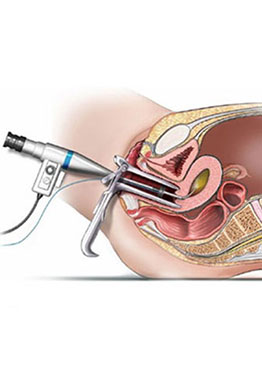

This is also called as key hole surgery.Telescope with fibre optic cable introduced through a port is used to visualize the abdominal and pelvic contents.

Visualisation of the endocervical canal and uterine cavity through an endoscope is known as Hysteroscopy.

It is the assessment of within the belly utilizing a fine telescope (Fig-8/9),Hysteroscopy Treatment in Ghatkopar. A little telescope is embedded through the vagina and cervix into the depression of the belly, Hysteroscopy Treatment in Ghatkopar. For the most part this is done under general anesthesia.